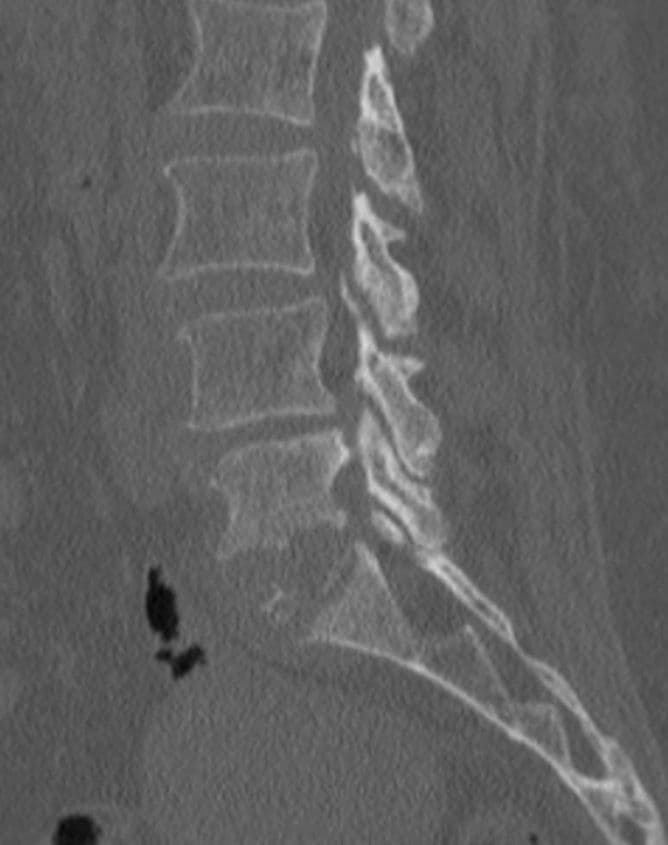

Infective Spondylodiscitis at L5-S1

A 65-year-old female presented with severe low back pain that had been progressively worsening over several weeks, resulting in significant difficulty in ambulation and restriction of daily activities. Clinically, she exhibited localized tenderness in the lumbosacral region with painful spinal movements. Her condition raised strong suspicion of an underlying spinal infection. Subsequent laboratory investigations revealed elevated inflammatory markers, supporting an infective etiology.

Imaging studies, including MRI and plain X-rays, confirmed the presence of spondylodiscitis at the L5-S1 level, characterized by destruction of the vertebral end plates and narrowing of the intervertebral disc space. There were also early signs of instability at the lumbosacral junction. The progressive bony destruction was concerning, as it posed risks of persistent pain, deformity, and potential neurological compromise if left untreated. The combination of advanced age, severe functional disability, and the destructive changes necessitated surgical management. A plan for posterior instrumentation with stabilization, debridement, and bone grafting was made to control infection, restore stability, and promote fusion.